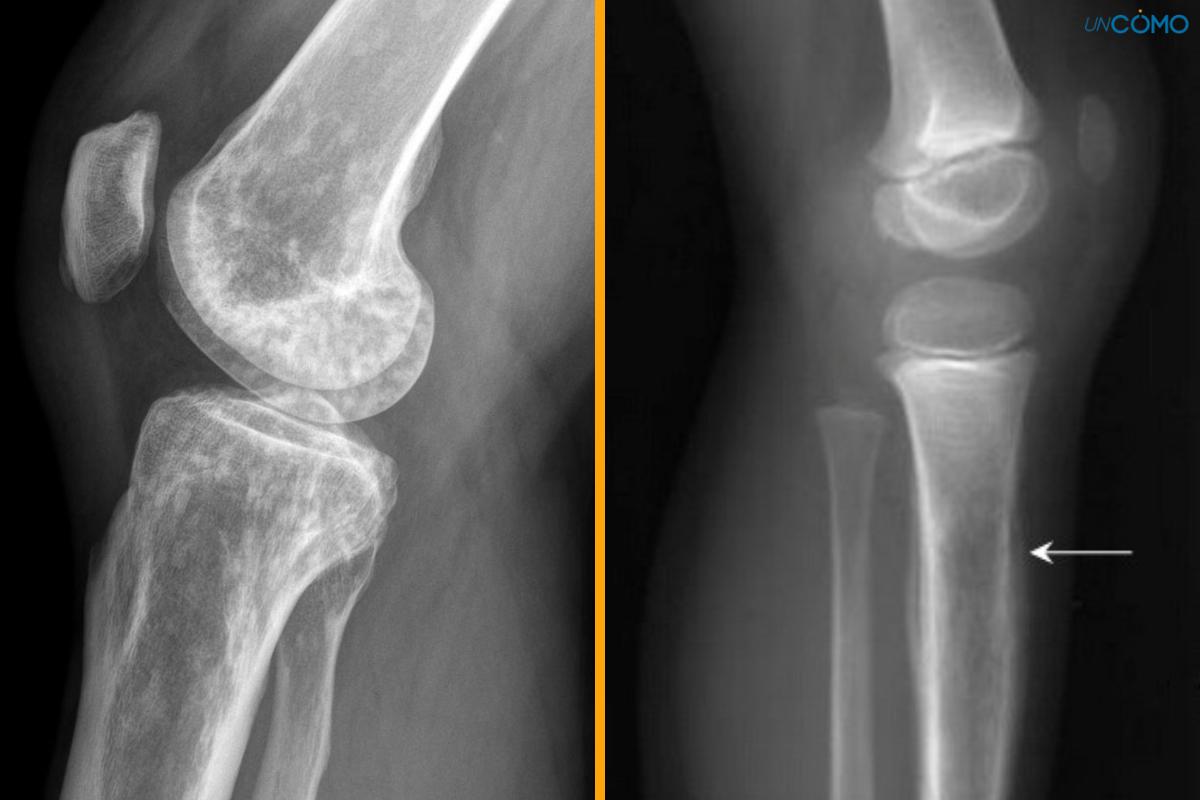

El sarcoma de Ewing es un tumor canceroso que se desarrolla en los huesos o en la parte del tejido que rodea los huesos, es decir, el tejido blando. Frecuentemente, crece en las piernas, las costillas, la pelvis, la columna vertebral o los brazos. También puede llegar a expandirse a los pulmones, la médula ósea y los huesos.

Pese a que este tipo de cáncer puede surgir en cualquier rango de edad, su afectación es más común en niños y adolescentes. De hecho, es segundo tipo de cáncer de hueso que más afecta a los niños. La mitad de los tumores asociados al sarcoma de Ewing aparecen en niños y jóvenes en edades de entre 10 y 20 años, aproximadamente.

¿El sarcoma de Ewing tiene cura? - Síntomas del sarcoma de Ewing